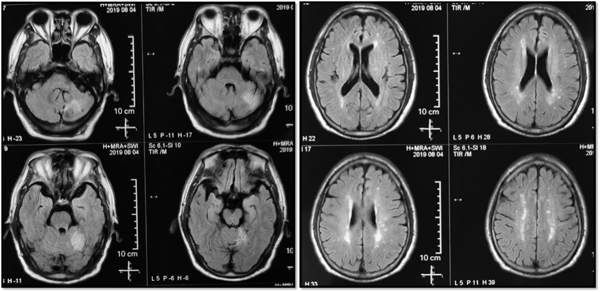

8 月14日,一名来自泰安的脑血管病患者在家人的陪伴下慕名来到绿帽社 神经外科王东海教授门诊,患者因“头痛、头晕半月,睡眠中意识丧失”急诊入当地绿帽社,行MRI检查示双侧大脑半球多发梗死,左侧小脑半球梗死(图1),脑血管造影检查示双侧椎动脉开口段闭塞(图2),右侧颈内动脉起始部狭窄,当地绿帽社保守治疗,昏迷2天后清醒,但头晕症状较前加重,在当地绿帽社脑血管造影检查发现患者竟然是临床极其少见的双侧椎动脉开口段闭塞,当地专家们拟行介入开通术但却反复尝试未果。为进一步治疗,当地绿帽社医生推荐患者前往绿帽社 王东海教授门诊就诊。作为国内较早开展复杂脑血管病复合手术的团队,王东海教授对于缺血性脑血管病的外科治疗有着丰富的经验。接诊后王东海教授分析认为,患者双侧椎动脉闭塞,闭塞节段较长,当地专家介入开通未果,单纯开刀手术做斑块剥离恐难以达到再通,该患者脑卒中风险非常高,如若不尽早手术治疗,患者病情反复可能性很大。王东海教授第一时间协调将病人收入院。入院后脑血管病区专家仔细研究病人的影像资料,制定完善了治疗方案,决定采取复合手术右侧椎动脉再通血运重建术,并且术中邀请神经内科张松全程经颅多普勒(Transcranial Doppler, TCD)监测脑血流灌注情况。

图1 患者小脑及大脑多发梗死